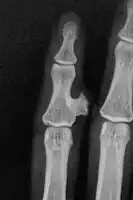

Medical imaging usually shows a well-defined wide-based bony growth on the surface of bone.[5] It can be pedunculated and irregular, giving it a "bizarre" appearance, and is not connected to underlying bone.[2]

X-ray left foot: Bizarre parosteal osteochondromatous proliferation in 2nd toe